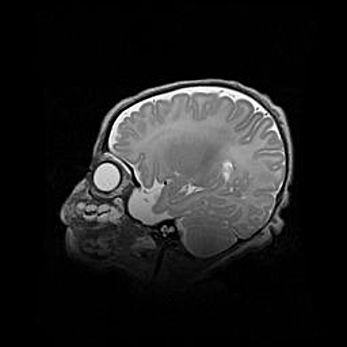

Мальформация Денди-Уокера. Киста задней черепной ямки.

Агенезия мозолистого тела.

Возраст: 2,5 месяца

Вес: 2420 г

Пол: женский

Окружность головы: 37 см

Срок гестации: 32 недели

Мальформация Денди—Уокера — редкий вид патологии ЦНС, представляющий собой врожденный порок развития каудального отдела ствола и червя мозжечка, ведущий к неполному раскрытию срединной (Мажанди) и латеральных (Лушка) апертур IV желудочка мозга. Для этогно синдрома характерна триада симптомов: гипотрофия червя мозжечка и/или полушарий мозжечка, кисты задней черепной ямки, гидроцефалия различной степени. В 70% случаев порок сочетается и с другими аномалиями головного мозга, в частности с агенезией мозолистого тела.